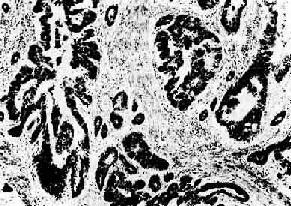

(1)腺癌(adenocarcinoma):较多见于胃肠、胆囊、子宫体等。癌细胞形成大小不等,形状不一、排列不规则的腺样结构,细胞常不规则地排列成多层,核大小不一,核分裂像多见(图7-13)。当腺癌伴有大量乳头状结构时称为乳头状腺癌;腺腔高度扩张呈囊状的腺癌称为囊腺癌;伴乳头性生长的囊腺癌称为乳头状囊腺癌。

图7-13 腺癌(胃)

癌细胞排列紊乱,多层,形成大小不等、形状不规则的腺样结构,浸润于胃壁组织内